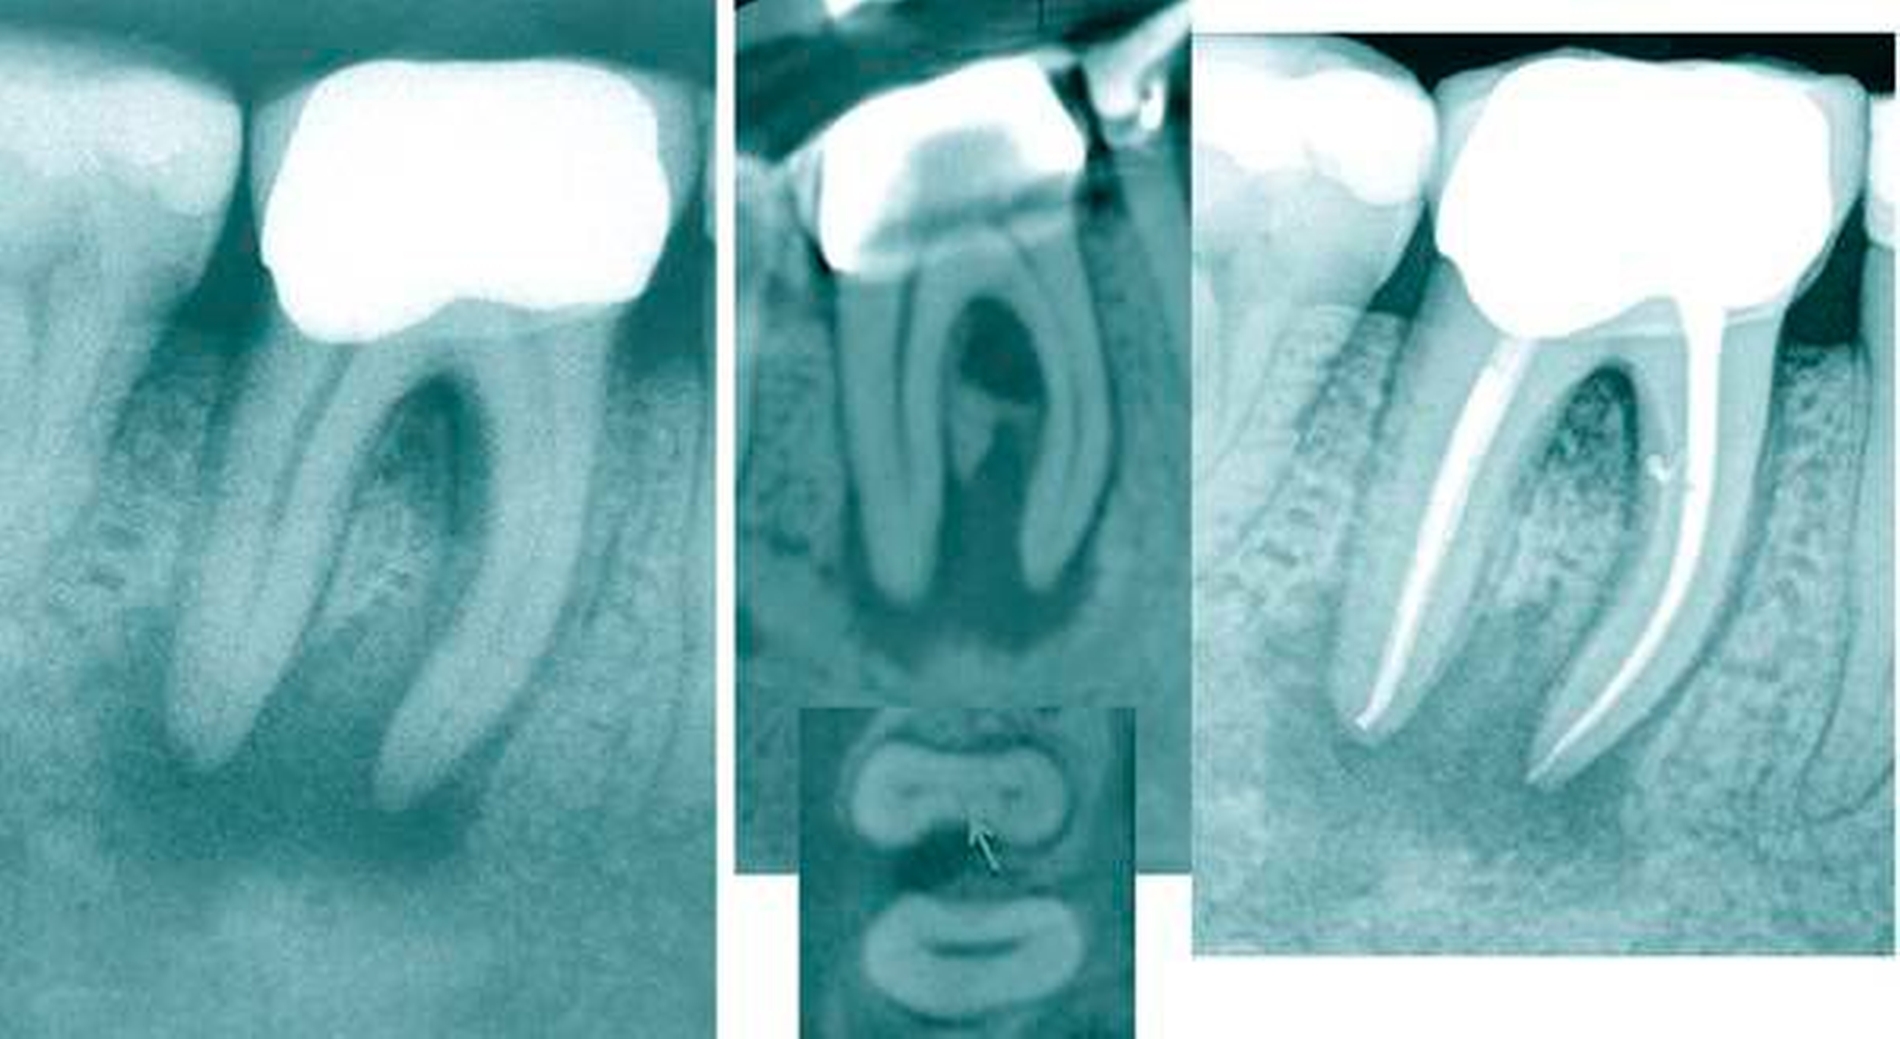

In den ersten Unterkiefer-Molaren wurde das Vorkommen von drei Kanälen mit einer Häufigkeit von circa 61 Prozent, von vier Kanälen mit 36 Prozent und von mehr als vier Kanälen mit nur etwa 1 Prozent beschrieben [Cantatore et al., 2009]. Mittlerweile wurden neuere Daten mittels Mikro-CT aus komplizierteren Kanalanatomien mesialer Wurzeln gewonnen und analysiert [Harris et al., 2013]. In etwa 9 Prozent der untersuchten Zähne wurden sogar vier Kanäle in einigen Wurzelabschnitten der mesialen Wurzel gefunden. In der mesialen Wurzel werden am häufigsten zwei Kanaleingänge und zwei Ausgänge gefunden, gefolgt von der Konfiguration zwei Kanaleingänge und ein gemeinsamer Ausgang [de Pablo et al., 2010].

In der distalen Wurzel der unteren ersten Molaren zeigt sich ein sehr viel komplexeres Bild von Kanalkonfigurationen (Abbildung 5), die schwer einer Klassifizierung zugeordnet werden können [Filpo-Perez et al., 2015].